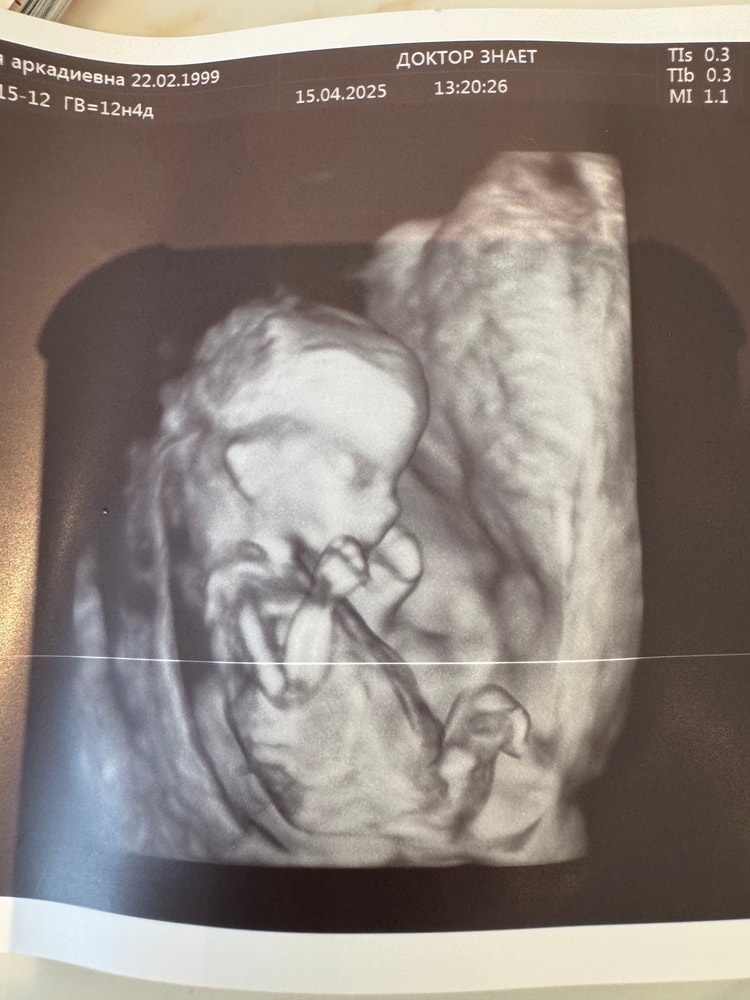

Анализы, скринингиДо сих пор не верю, что уже прошло 12 недель, с ребёнком видимо время летит очень быстро😀сходила на узи, врач конечно же зная , что у нас есть мальчик, предположила , что я хочу девочку и была права, но точно сказать не могла , так как не понятно, но с сыном на этом сроке уже сказали, что мальчик, а тут не понятно. Как думаете на кого больше похожа ?🙏🏻🙈

Какой курносый малыш, прелесть❤️ мне не предполагали ни на одном, у нас вообще такого не говорят, только на втором, в 20 недель( но мальчиков я видела сама, у них бугорок вверх торчал. Сейчас лежал параллельно спинке, по узи пока что тоже девочка, но не точно

Арина Амирова , снизу у моей девочки в 12н такой приличный «писюн» был. Но наклон совершенно другой. У сына он между ног видно, как вверх вздергивается, а у девочки чисто ровный. По этому снизу на этом сроке не смотрят.